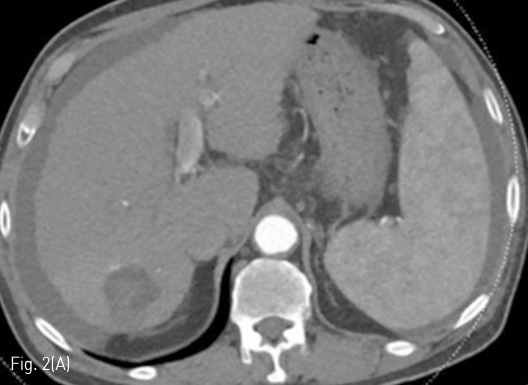

Fig 2A

Follow up liver CT 11 months after RFA. (A-D) There is a connection (arrows) between a branch of the S7 segmental hepatic artery and right posterior portal vein.

Fig 2B

정기적 추적검사로 시행한 자기공명영상 (MRI)에서 7번 간분절(S7)에 간담도기에 저신호강도로 보이고 확산강조영상에서 고신호강도로 보이는 간암으로 의심되는 결절이 발견되어 고주파 열치료술이 시행되었다 (Fig. 1A, 1B). 10개월 후 추적검사로 시행한 전산화 단층 촬영의 동맥기 영상에서 우측 후방 간문맥이 주위 간동맥만큼 조영증강이 되는 소견을 보이고 있다(Fig. 1C, 1D). 동맥기 영상에서 간동맥과 간문맥 사이에 연결성이 보여 간동문맥단락이 의심되는 소견을 보이고 있다(Fig. 2).